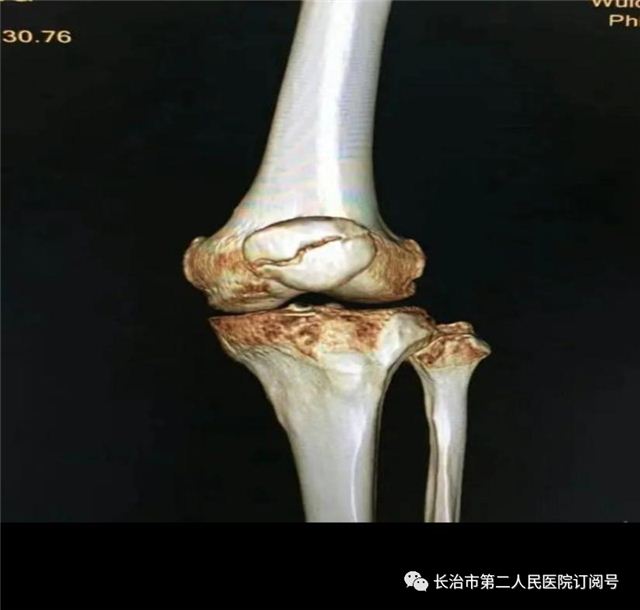

临床处理

手术治疗